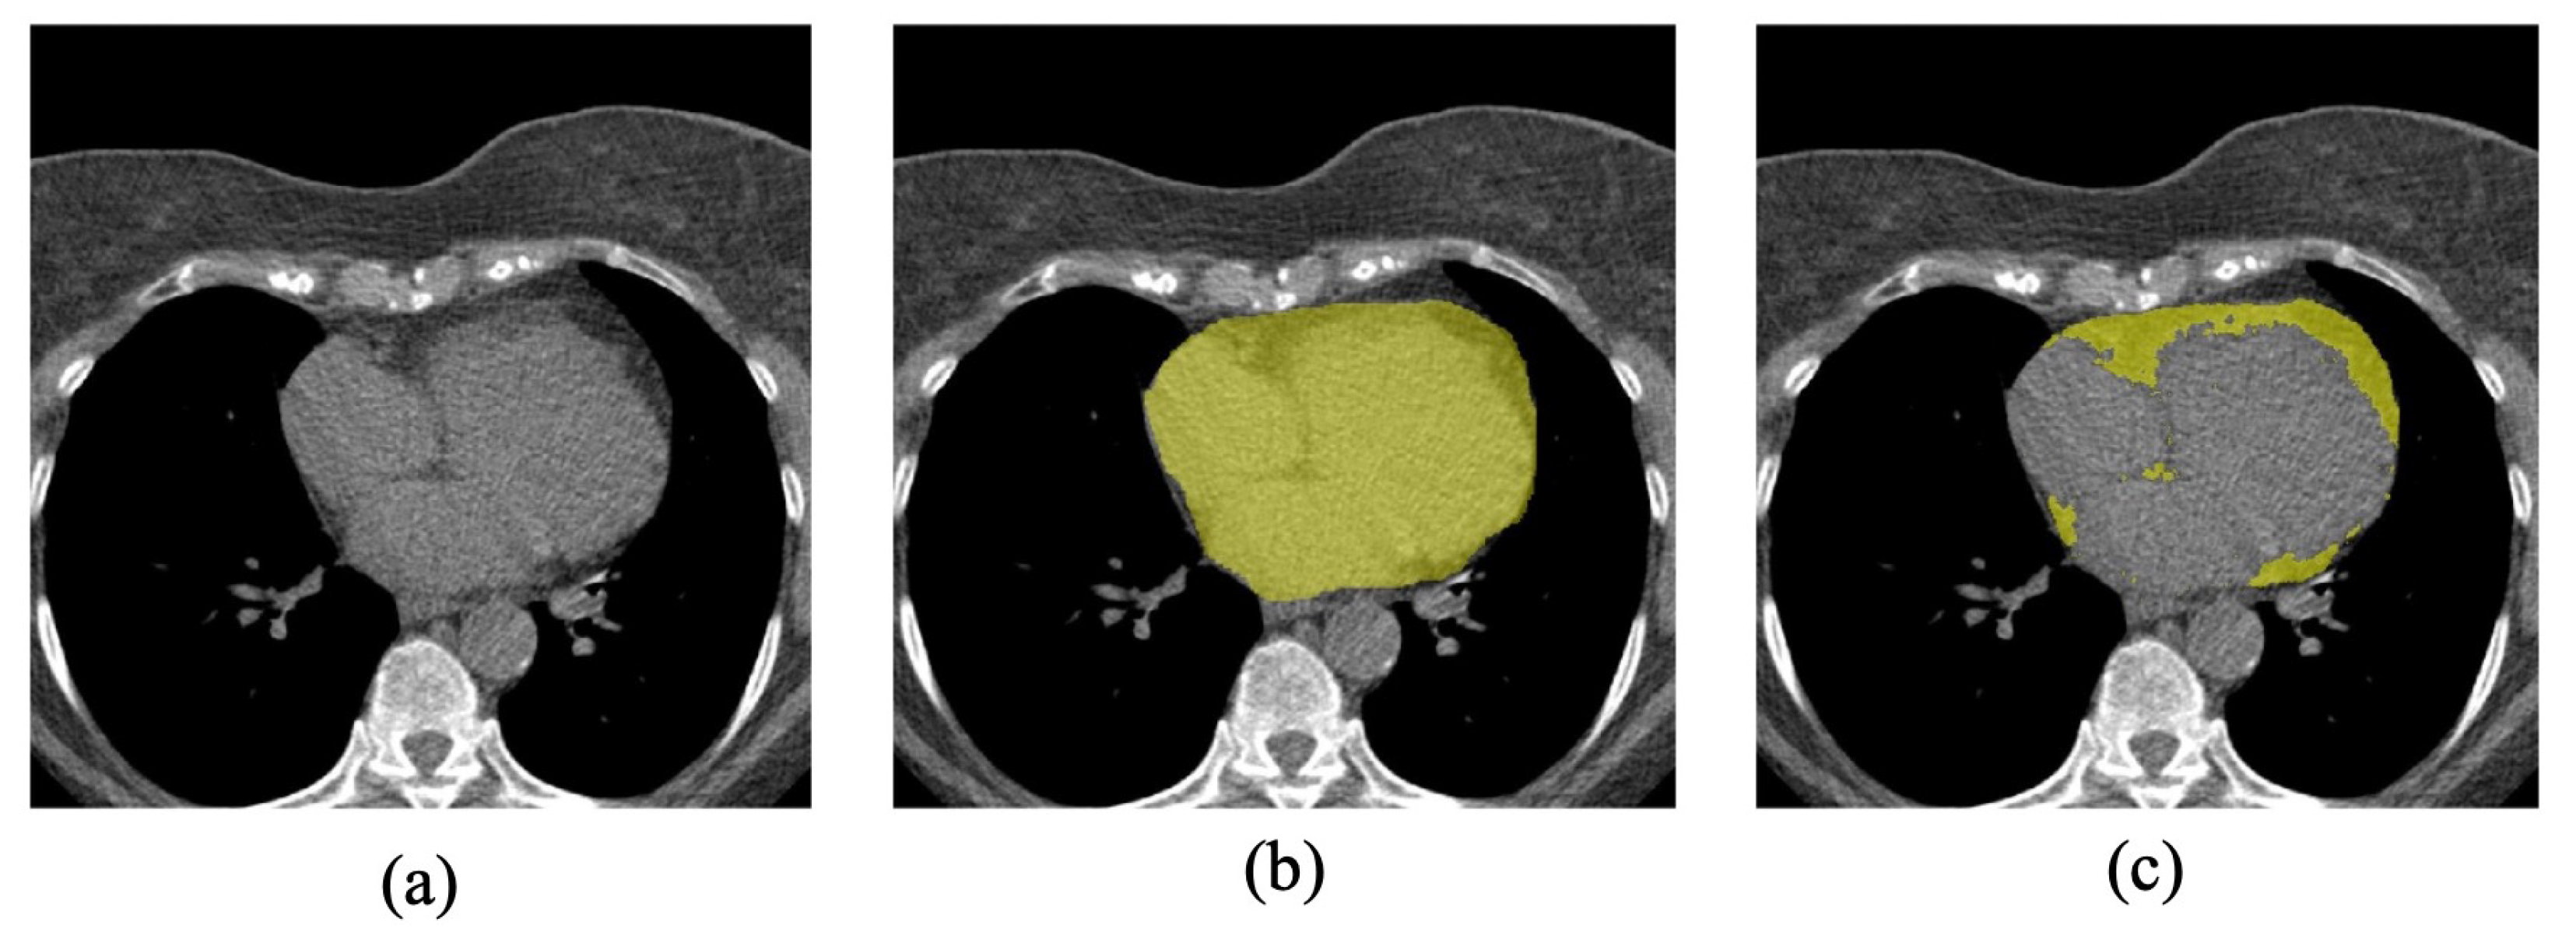

EAT is characterized as fatty-like tissue intensity positioned between the myocardium and the visceral pericardium, with intensity limits ranging from −190 HU to −30 HU [39]. Manual annotation of EAT in CT scans can be accomplished through two primary methods: (a) annotating the region within the pericardium and then applying HU value thresholding to extract adipose tissue [11], or (b) directly annotating the region of EAT and utilizing HU value thresholding to generate final labels [12]. Due to the use of low-dose CT in our study, the second annotation strategy can be particularly challenging due to the reduced visibility of fat tissue and increased noise. As such, to ensure feasibility and efficiency, we chose the first annotation strategy. The labels were annotated by an experienced radiologist using the open-source medical imaging processing software 3D Slicer 4.10.2 (https://www.slicer.org/) (accessed on 19 February 2019) [40]. Two kinds of label maps were obtained, as shown in Figure 1: (1) the region inside the pericardium (in the second column, colored in yellow), and (2) the EAT volumes (in the third column, colored in yellow). To reduce the workload, all the annotations were made in the axial view semi-automatically. The radiologist annotated the region inside the pericardium on some 2D slices, and the annotations in between were generated automatically with the ’fill between slices’ effect of the 3D Slicer. Finally, the radiologist checked and corrected the generated annotations. To obtain the EAT, the thresholding of −190 HU to −30 HU was applied, and then the morphological operations of erosion and dilation were used to reduce the noise.

Figure 1.

(a) An example of a CT slice, (b) the binary label of the region inside the pericardium, and (c) the pixel-wise EAT label.